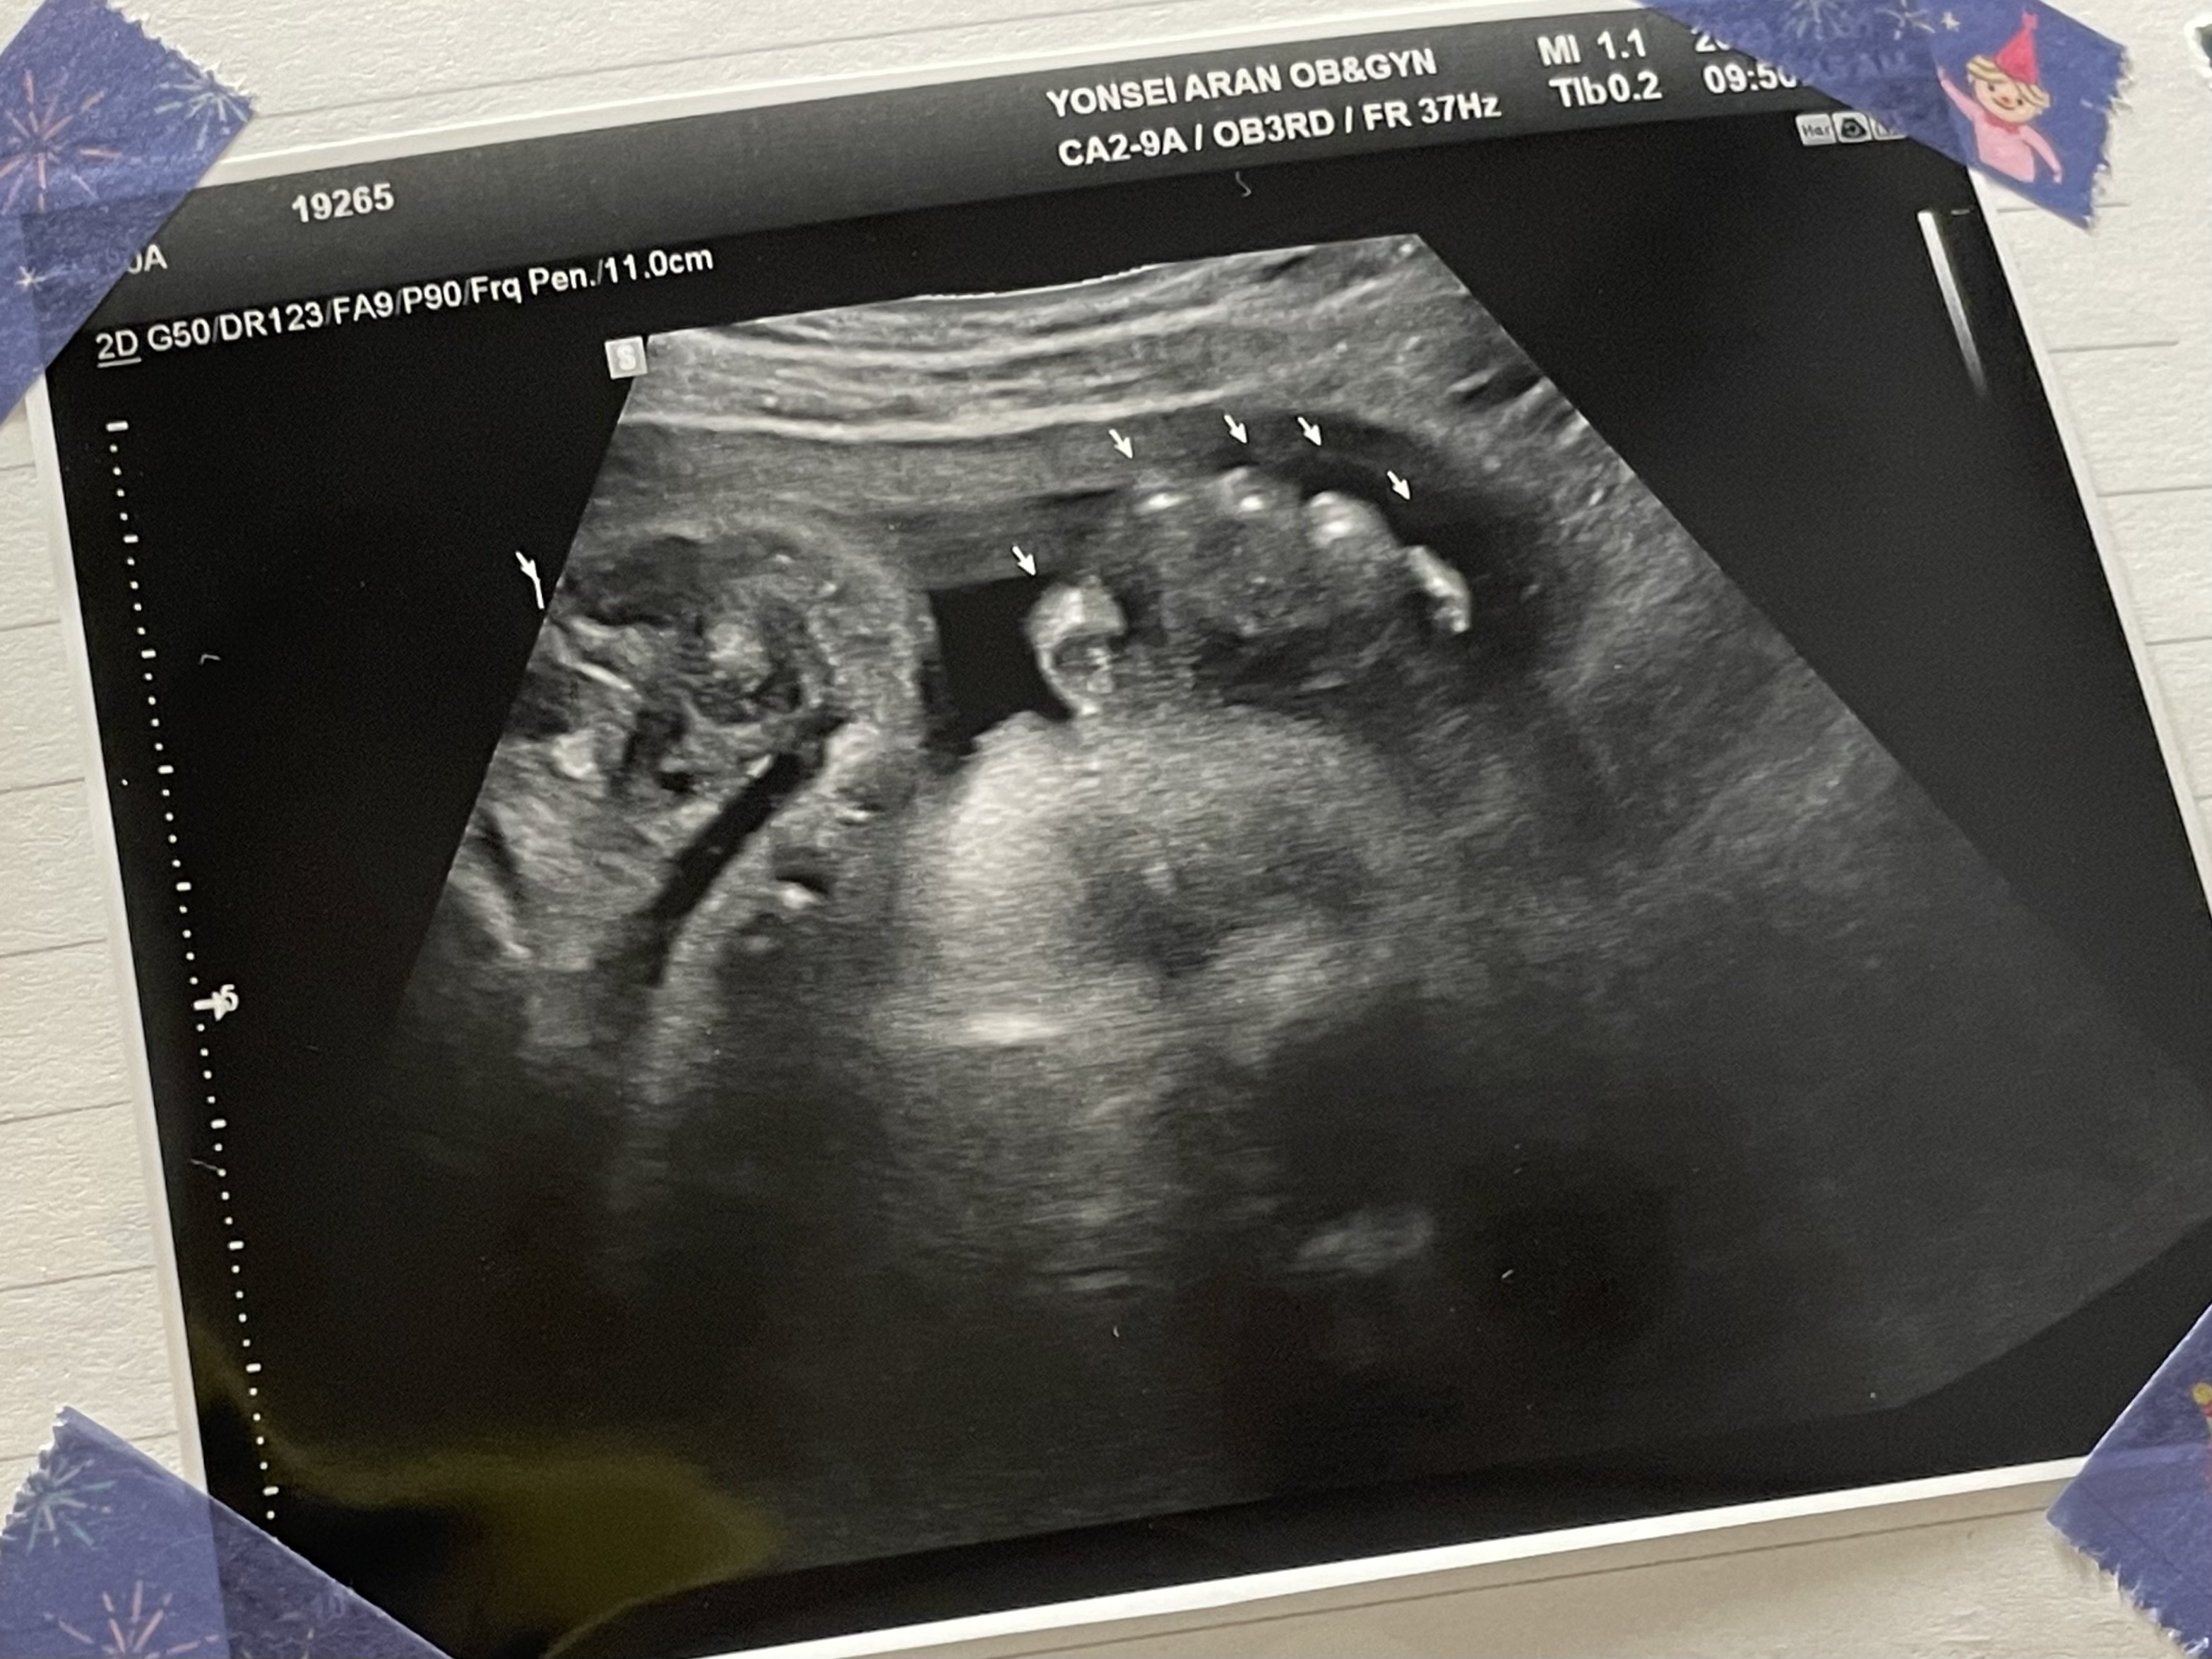

정기검진을 받았다.

손가락이 그 사이 통통해져 있었다.

배가 너무 무겁고

내 몸무게가 훅훅 늘어서

애기가 거대아가 되어있으려나 하고 걱정했는데

1.6kg 조금 넘는 몸무게로

평균 이하라고 하셨다.....

양수가 정상범위긴 하지만 좀 적다고 물을 많이 마시라고 하셨다.

이제부터 2주마다 한번씩 내원하면 된다고 하셨다.